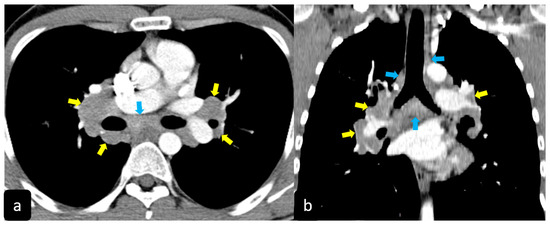

2.2. Typical and Atypical Manifestation of Pulmonary Sarcoidosis at HRCT